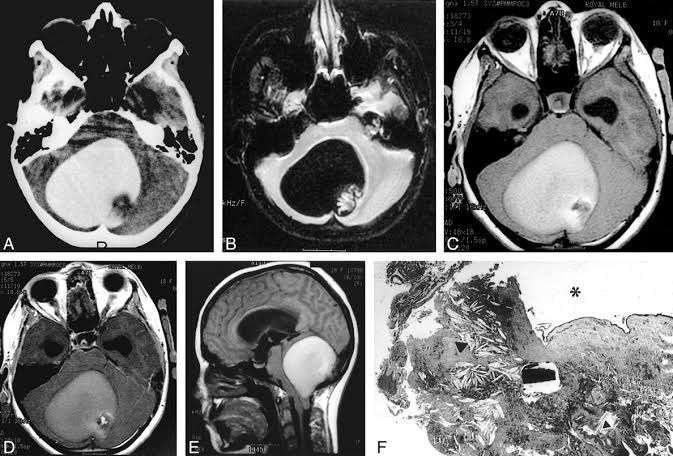

A dermoid cyst is a developmental anomaly characterized by a saclike growth that is present at birth. It grows slowly and are not tender unless ruptured. It may contain structures such as hair, fluid, teeth and usually occur on the face, inside the skull, on the lower back, and in the ovaries. Dermoid cysts account for ~0.5% of all primary intracranial tumors and are slightly more common in females. Intracranially, they are typically located in the midline and grow towards one side or the other. Locations include: midline sellar and suprasellar parasellar frontonasal region posterior fossa/vermis Credits : https://radiopaedia.org/articles/intracranial-dermoid-cyst-1 http://www.ajnr.org/content/22/10/1970